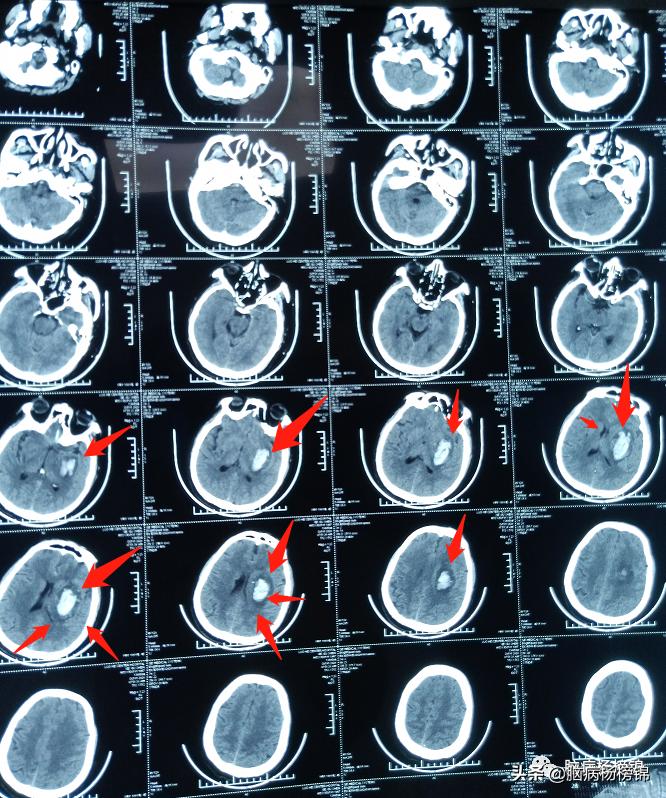

漯河市第一人民医院急诊颅脑CT,脑出血。

保守治疗六天,病情稳定。